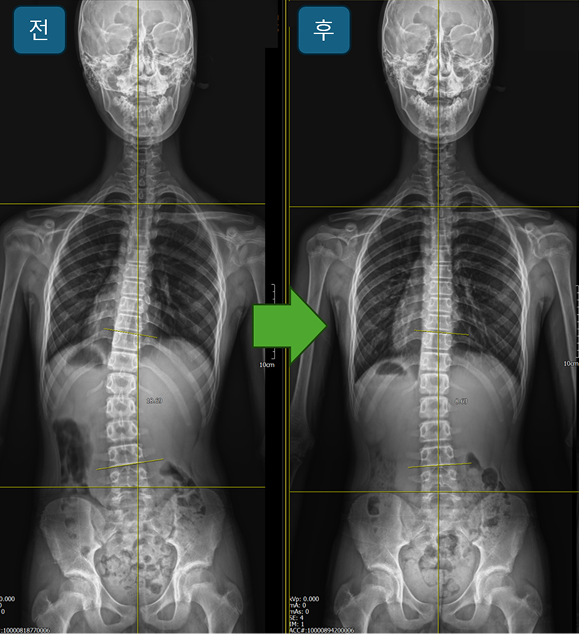

교정사례

조은정형외과의원의 깔창 교정 케이스